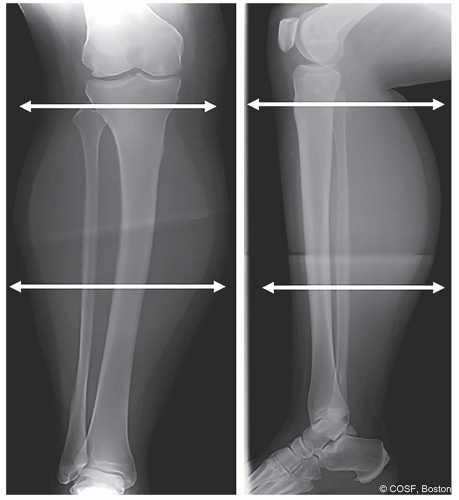

Ring size can be preoperatively templated, based on the soft tissue shadow of the anteroposterior (AP) and lateral x-rays of the leg (Figure 25.2)

Appropriate size rings should be confirmed intraoperatively prior to placement to ensure that rings do not impinge on soft tissue around the full circumference of the leg (ring should remain at least 2 cm from the skin surface to account for postoperative swelling)

A two-thirds ring is typically chosen at the proximal tibia to allow knee flexion beyond 90° (due to posterior opening), and full rings are used in the tibial shaft and distal tibia

Proximal and distal rings can be different sizes